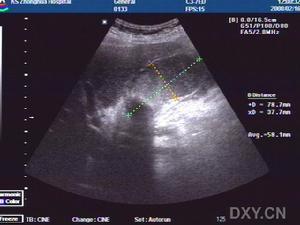

急性膽囊炎--B超當醫生檢查病人的腹部時,可以發現右上腹部有壓痛,並有腹肌緊張,大約在1/3的病人中還能摸到腫大的膽囊。化驗病人的血液,會發現多數人血中的白細胞計數及中性白細胞增多。B超檢查可發現膽囊腫大、囊壁增厚,並可見結石堵在膽囊的頸部。

3.B型超聲檢查,膽囊增大,囊壁增厚,可能可看到結石的影像。

3.B超檢查示膽囊增大,壁厚>3.5mm,內有強光團伴聲影。